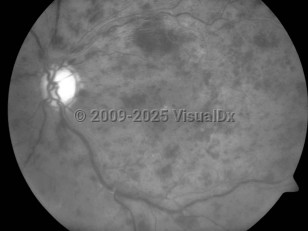

Central retinal vein occlusion - External and Internal Eye

The central retinal artery and vein share a common adventitial sheath as they exit the optic nerve head and pass through the lamina cribrosa. Often in CRVO, a rigid atherosclerotic artery impinges on the nearby vein, causing turbulence and predisposing to thrombus formation. With increased resistance of venous flow, the retina becomes ischemic and fluid leaks out of the vessels. Increased intraocular pressure could also cause turbulence of the central retinal vein and lead to thrombus formation and obstruction.

The occluded central vein can lead to intraretinal hemorrhage, exudation of fluid, varying levels of ischemia, and neovascular complications such as neovascular glaucoma. CRVO is commonly classified by severity into 2 forms: the nonischemic form of CRVO, which is milder and more common, and the ischemic form, which results in more severe retinal damage and vision loss. In ischemic CRVO, more than 90% of patients have vision of 20/400 or worse. One-third of patients with the nonischemic type progress to the ischemic type.

Iris neovascularization, which is associated with neovascular glaucoma, occurs in up to 60% of patients with the ischemic form, usually 3-5 months following the obstruction. The main risk factors for development of neovascular glaucoma after a CRVO are the extent of capillary nonperfusion, poor visual acuity, severe venous tortuosity, and retinal hemorrhage.